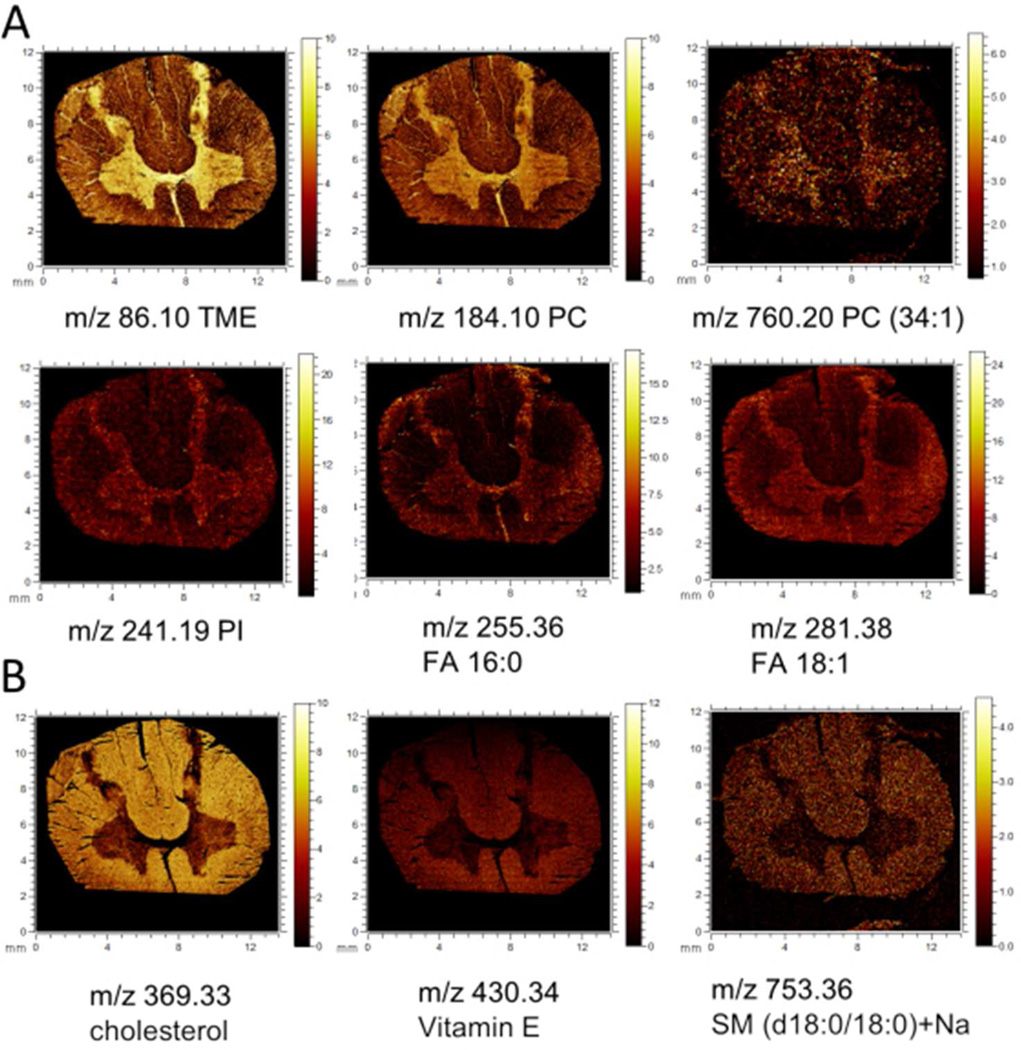

Indeed using a top-down image analysis approach, the characteristic outline of the grey and white matter, respectively, has been observed in the second principal component and the third MAF factor, respectively (Fig. 1A). From the eigenvectors (loadings) of the corresponding PC or MA factor, the variables, i.e. m/z values, can be obtained that contribute most to the respective eigenvalues (i.e. PC- or MAF score) (Fig. 1B, SI Fig. 1,2). The calculated data for positive and negative mode show characteristic localization of various lipid species. Here phosphatidylcholine (PC) headgroup and intact phospholipids were detected in positive mode localized to the grey matter. In negative mode, fatty acids (FA) and phosphoinositols (PI) were found to be increased in the gray matter region (Fig. 2A, SI Fig.2). In contrast, localization of cholesterol derivatives, vitamin E and sphingomyelins (SM) to the white matter region were observed (Fig.2A), all detected in positive mode. In negative mode, predominantly cholesterol species (m/z 385.36, [M-H]−) and vitamin E (m/z 430.29,C29H49O2, [M-H]−) were found increased in the white matter.

Figure 2.

Single ion images of individual molecular species that localize to distinct anatomical regions as revealed by multivariate images analysis. (A) Lipid species that localize to the grey matter including trimethylethylenimine (m/z 86.1, [C5H12N]+,), phosphatidylcholine headgroup ([C5H15PO4N]+, m/z 184.09), phospholipids in positive mode. In negative mode, phosphoinositol lipids (PI) as indicated by the PI headgroup (m/z 241.19, [C6H11O8P]- as well as fatty acids (FA) such as palmitic acid (FA 16:0, m/z 255.36, [C16H31O2]−) and oleic acid (FA 18:1, m/z 281.38, [C18H33O2]−) were found increased in the grey matter. (B) Chemical species that localize to the white matter include cholesterol (m/z 369.33, [M+H-H2O]+), vitamin E (C29 H50O2, [M+H]+), and sphingolipids such as sphingomyelin (m/z 753.36, SM(d18:0/180) [M+Na]+).